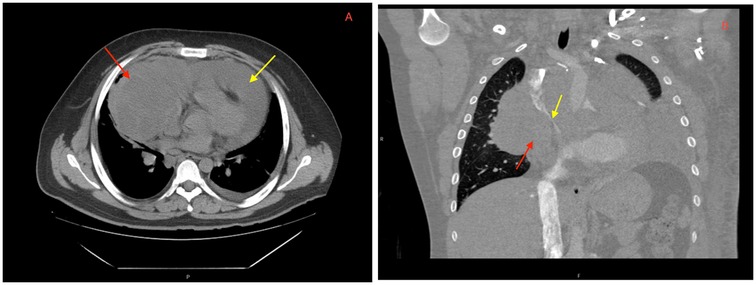

On hospital day 2, the patient developed worsening tachycardia and respiratory distress. Physical examination noted a tachycardia rate of 130 bpm with clear heart sounds and a blood pressure of 101/68 mmHg; JVD was present, and pulsus paradoxus was appreciated with a respiratory variation of systolic blood pressure (SBP) >20 mmHg. Repeat CT showed interval enlargement of the mediastinal mass with right atrial and RV compression, significant narrowing of the main pulmonary arteries, and compression of the superior vena cava (Figure 2). Repeat echocardiogram showed minimal reaccumulation of pericardial fluid but redemonstrated the large mediastinal mass, with compression of the right ventricle causing significant respiratory inflow variability in the mitral valve (40%), tricuspid valve (30%), and aortic valve (20%) spectral Doppler velocities with septal bounce that was concerning for tamponade physiology (Figure 3). He was resuscitated with 1 L of lactated Ringer's solution and brought to the ICU for stabilization. Conservative measures were unsuccessful in reversing his respiratory distress, which was thought to be secondary to a combination of imminent tamponade, pulmonary artery compression, and significant left lung atelectasis due to compression from the space-occupying lesion. Increasing oxygen requirements and respiratory fatigue prompted intubation and mechanical ventilation. The decision-making process involved cardiothoracic surgery, which deemed the patient to be a poor surgical candidate because of the unacceptable risk of cardiopulmonary collapse with general anesthesia.

Figure 2

CT imaging showing a (A) large mediastinal mass (red arrow) and pericardial effusion (yellow arrow) on presentation. Repeat CT angiography post-pericardiocentesis (B) redemonstrating a mediastinal mass (red arrow) abutting the right atrium and ventricle with significant narrowing of the superior vena cava (yellow arrow).